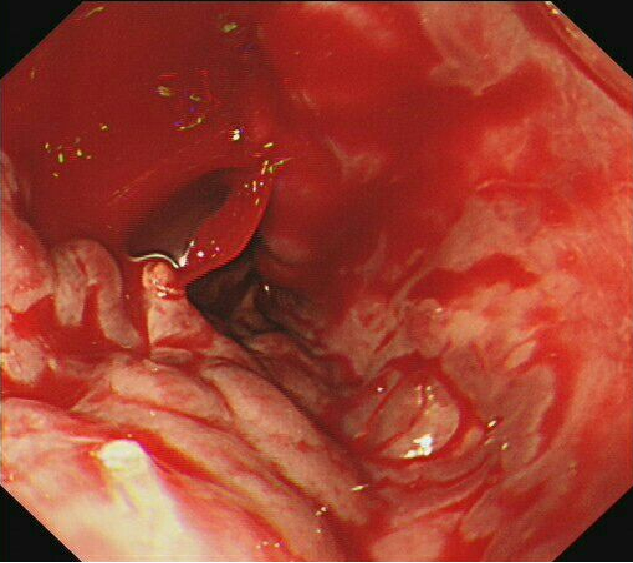

镜下果然看到他的食管静脉重度曲张并破裂,破口呈喷射状出血,内镜视野